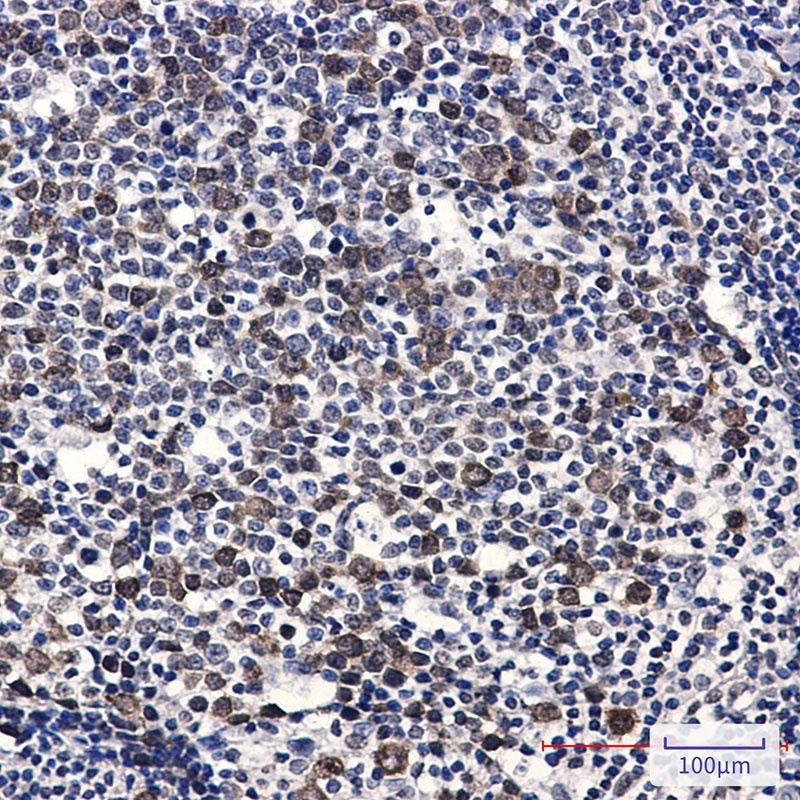

Phospho-CDK2 (Thr14) Rabbit mAb抗体

Phospho-CDK2 (Thr14) Rabbit mAb

CDK2

IHC-P, IP, WB

应用稀释比例:WB: 1/500-1/1000 IHC: 1/50-1/100 IP: 1/20